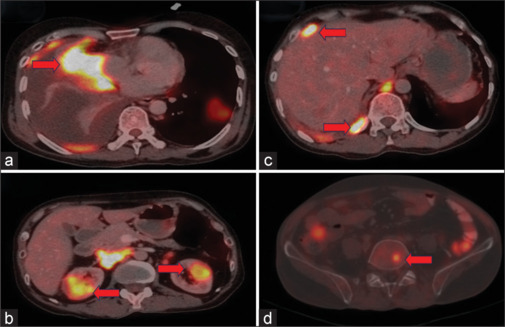

Metastases from squamous cell carcinoma of the lung typically occur in the brain, liver, adrenal glands, bone, and regional lymph nodes. It is exceedingly uncommon to encounter multiple rare sites of metastasis from a single primary neoplasm. Herein, we describe a case of a 44-year-old male diagnosed with squamous cell carcinoma lung with pituitary and renal metastasis detected on 18F-FDG (Fluorodeoxyglucose) PET/CT. 18F-FDG PET/CT is the standard of care and is an integral part of the clinical staging of patients with lung cancer. According to published literature, the incidence of symptomatic pituitary and renal metastasis from squamous cell carcinoma lung is rare to find with incidences <1% and 5%, respectively. The revelation of rare sites of metastasis originating from primary squamous cell carcinoma lung, as reported in this case on FDG PET/CT, illuminates the exceptional rarity and intricacies in oncology. The exquisite sensitivity of FDG PET/CT enables the identification of occult metastasis in atypical anatomical locations, presenting a distinct advantage over conventional imaging modalities.